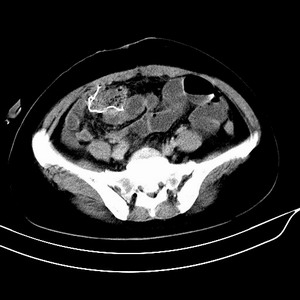

女 42岁 子宫肌瘤于外院术后两天,感腹胀。x线提示肠梗阻。

子宫肌瘤于外院术后两天,出现肠扭转梗阻,很明显。但右下腹部出现的线状高密度,是什么呢?有什么手术会有这样的物品呢?不会把电刀的导线遗留在腹腔吧!?

结果:术后纱布遗留,术后麻痹性肠梗阻肠梗阻

上面的图像是我们从手术室拿来的纱布做了个ct平扫,发现纱布里确实存在有一条致密影。后得知致密影是为防止手术时纱布遗留而设计。关腹时怀疑纱布遗留可做个床边透视或拍片可明确。